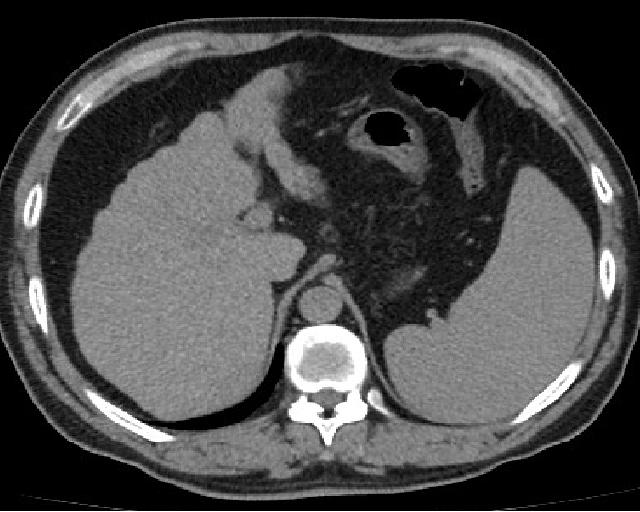

Hepatocellular carcinoma (HCC) presents with severe hepatomegaly and ascites.

Compared to primary liver tumors, liver metastasis is more common.

Clinical diagnosis of liver metastasis may reveal a nodular free edge of the liver and hepatomegaly.

Radiology of liver metastasis usually show numerous nodules in the liver.